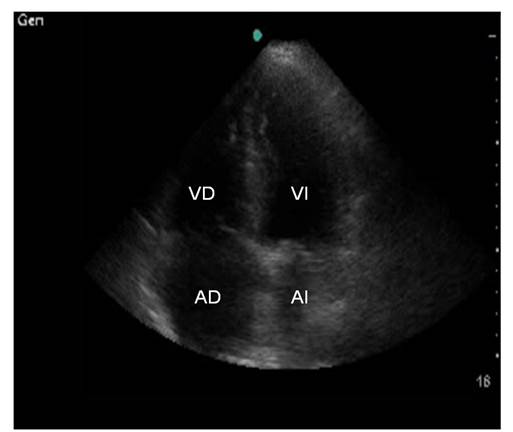

También se utilizaron visiones del eje apical en que se obtienen imágenes en 4 cámaras (ambas aurículas y ventrículos) y de 5 cámaras (ambas aurículas, ambos ventrículos y tracto de salida del ventrículo izquierdo) (Figura 2).

En nuestro estudio empleamos principalmente la ventana paraesternal izquierda y apical en 5 cámaras. (Figura 3)